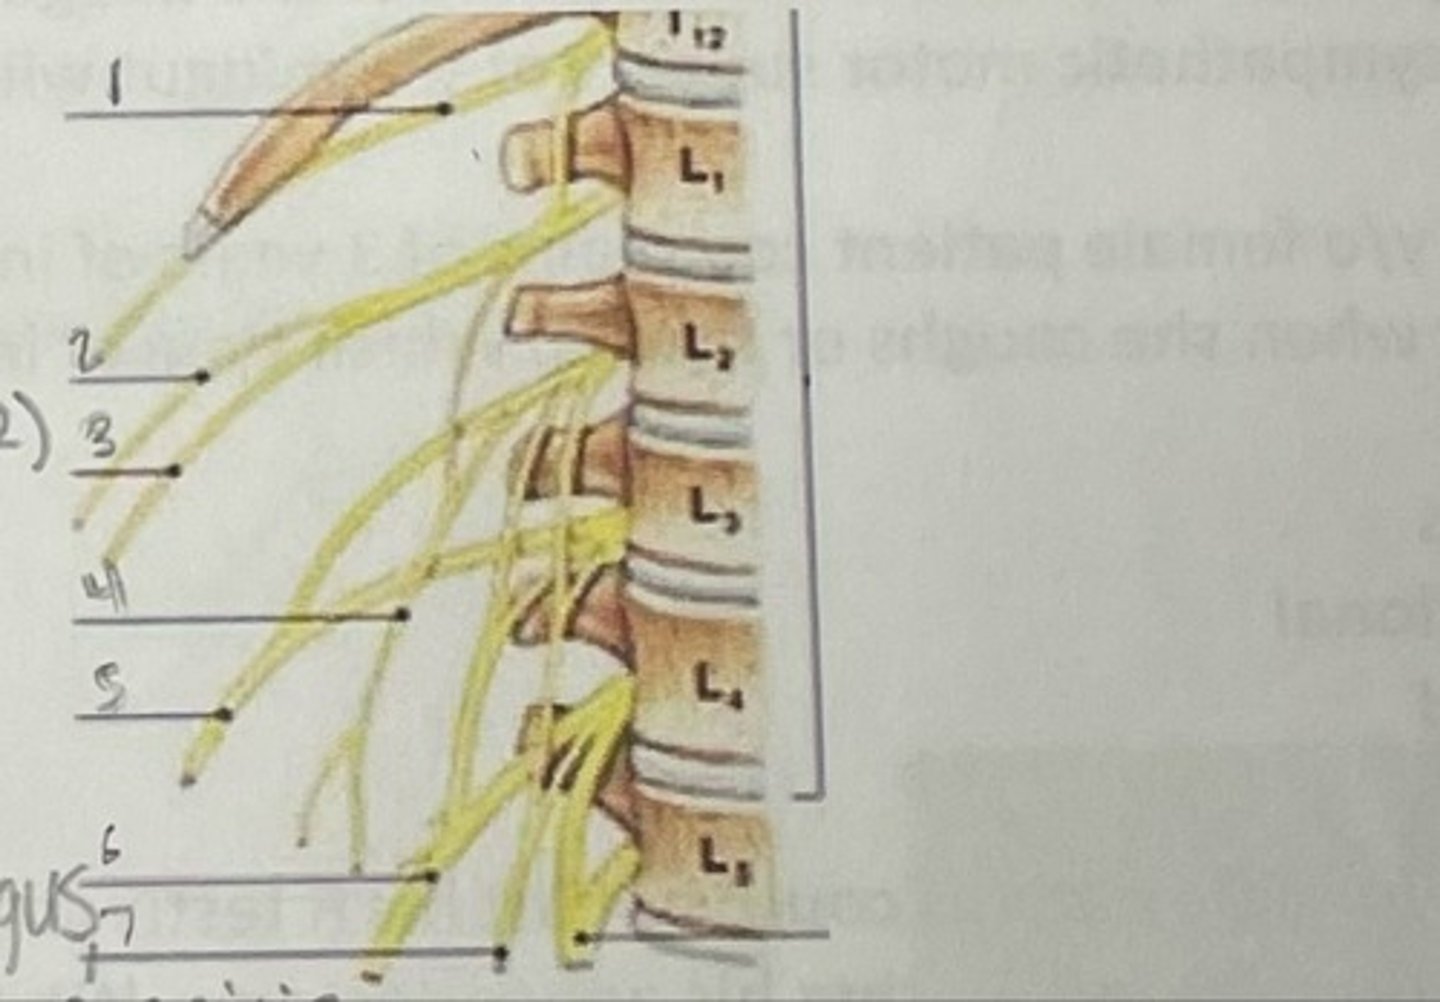

What is 1

Illiohypogastric nerve (T12/L1)

What is 2

Illioinguinal nerve (L1)

What is 3

Genitofemoral nerve (L1-L2) ; on top of psoas

What is 4

lateral femoral cutaneous nerve (L2-L3)

What is 5

Femoral Nerve (L2-L4)

What is 6

Obturator nerve (L2-L4)

What is 7

Renal artery